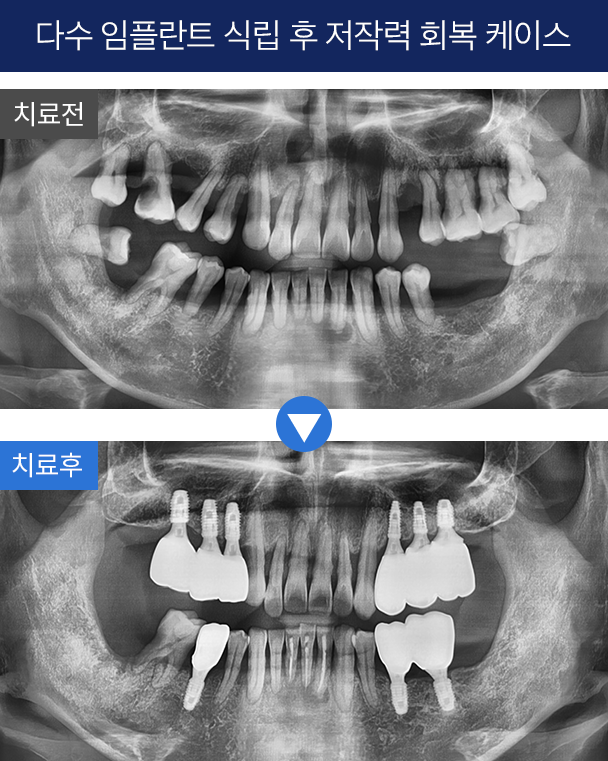

2